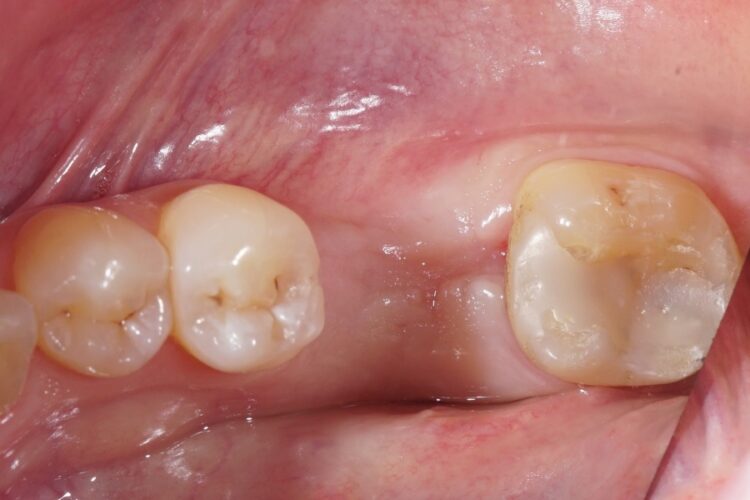

Клинический кейс имплантации

Все этапы: от компьютерной томограммы до установки коронки на имплант.

Установленный имплант: 4.5 мм на 11.5 мм

Коронка на имплант: дисиликат лития, винтовая фиксация, изготовлена в клинике за 3 часа.

Абатмент: индивидуальный титановый.

Длительность имплантации: 1.5 часа.

Промежуток от импланта до коронки: 3 месяца.

Заключение: проведена установка импланта с одновременной пластикой десны и формированием межзубных сосочков. В имплант установлен формирователь десны. Рана ушита. Швы необходимо снять через 10-14 дней. Даны рекомендации в послеоперационный период.

Установка коронки на имплант запланирована через 3 месяца.